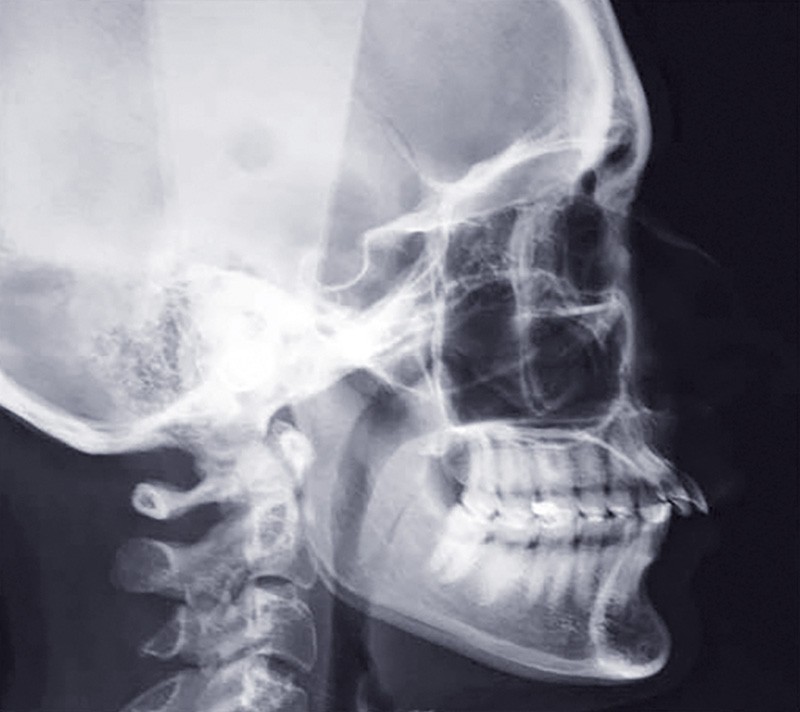

Charlotte présente donc une absence de 11, un surplomb et un recouvrement augmentés associés à une retromandibulie. La patiente a un profil convexe, hypodivergent avec une proalvéolie maxillaire et une classe II d’Angle. (fig. 1a à h). La radiographie panoramique confirme l’absence de 11 et la téléradiographique de profil, révèle une classe II squelettique (ANB : 6°, AoBo : 9 mm) par rétromandibulie ainsi qu’une proalvéolie maxillaire prononcée.

(I/Na : 40° I-Na : 7 mm) (fig. 2a et b).